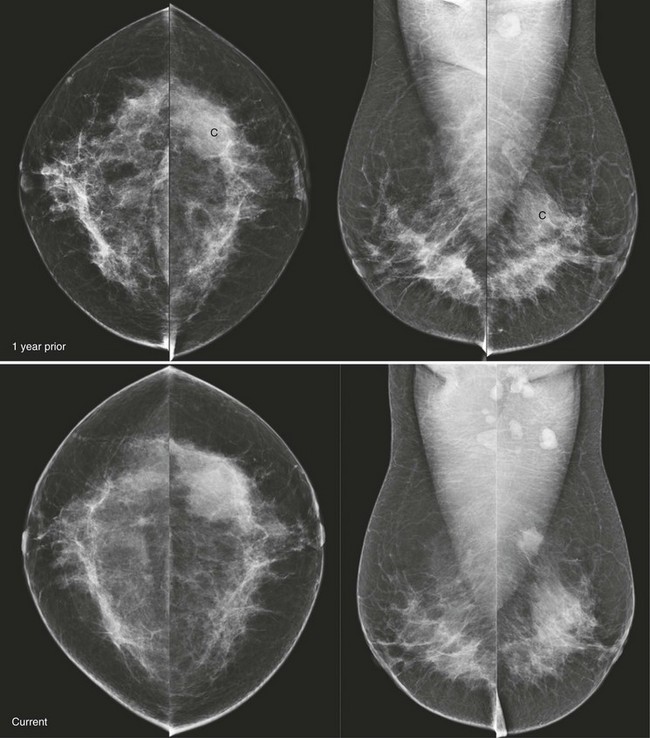

CASE 8-5. Screening mammogram of a 49-year-old woman with a comparison study from 1 year prior. A left breast cyst (C) was diagnosed by previous US. Can the rule of multiplicity be applied? What do you recommend?

CASE 8-5. There are two masses in the left breast, including the previously documented cyst (C), which has obscured margins. The more posterior mass is excluded from the screening CC view but is confirmed on the exaggerated craniocaudal lateral (XCCL) and mediolateral views (arrows). It has enlarged since the previous mammogram.

The rule of multiplicity should not be applied. The masses are unilateral. The posterior left breast mass has suspicious features (irregular shape, indistinct margins) and has clearly enlarged. There is a dense left axillary lymph node. US shows the known cyst and an adjacent, irregular hypoechoic mass, which was biopsied. Diagnosis: IDC grade 2.